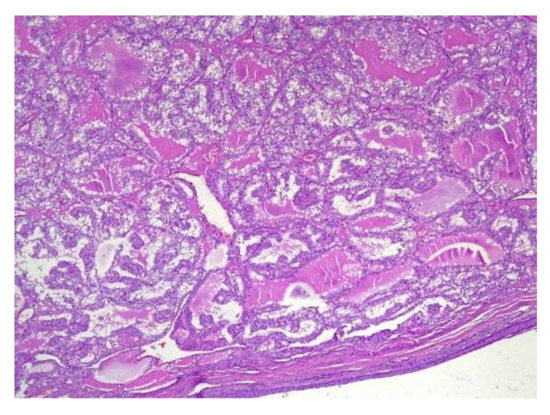

4.2. Histopathology Features